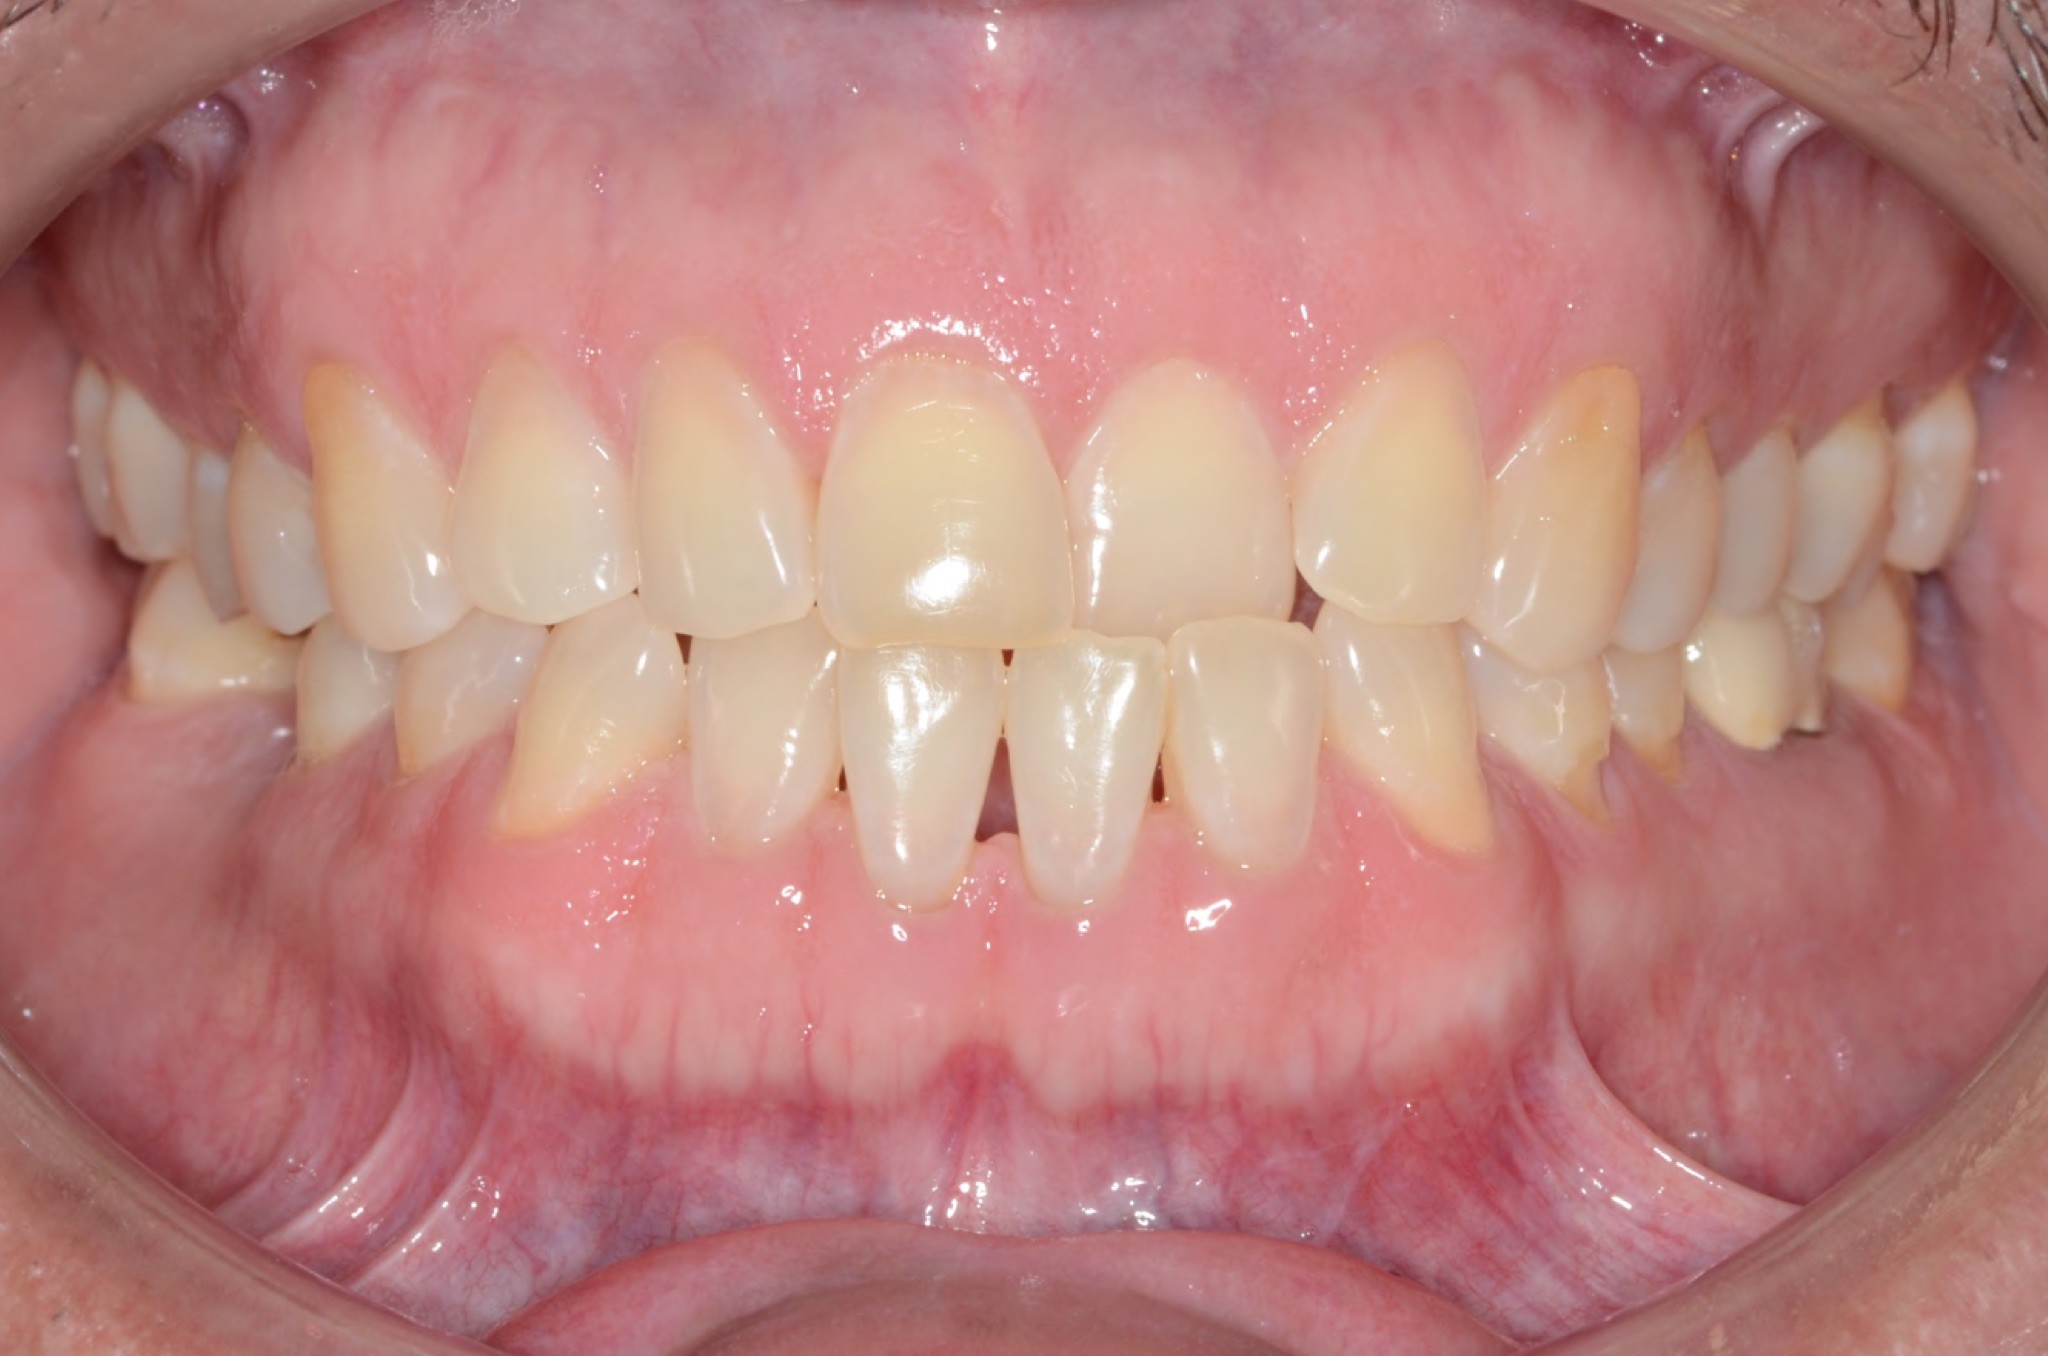

Initial treatment

INTRAORAL